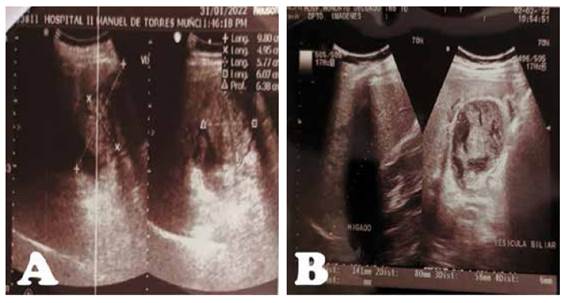

Presentamos el caso de un varón de 57 años, con antecedente de TBC pulmonar hace 20 años. Que hace 2 días presentó dolor en CSD, con irradiación a zona lumbar ipsilateral, asociado a náuseas y vómitos, y orinas oscuras. Por lo que acude a hospital, donde le realizan una ecografía abdominal, informada como VB con formación tumoral (Figura 1A), siendo referido a nuestro hospital. A su ingreso por emergencia, persistía el dolor en CSD a pesar de medicación analgésica. Al examen, paciente hemodinámicamente estable, dolor y masa palpable en CSD, y signo de Murphy positivo. La analítica de ingreso mostró una hemoblogina 14.0(VN:12-16gr/dl), hemograma 13000(VN: 5000-10000/mm3), INR 1.17, Bilirrubina total de 7.06 (a predominio directo 1.45) (VN:0.2-1.2mg/dl), fosfatasa alcalina(FA): 170(VN:27-100U/L), Gama-glutamil transferasa (GGTP): 409(VN:12-45U/L), amilasa en 66(VN: 0-120U/L), TGO 850(VN:<45U/L), TGP 980(VN:<45U/L). La ecografía fue informada como signos de CA litiásica con contenido biliar denso (Figura 1B). Se realizó una TC abdominal informada como CA litiásica con cambios inflamatorios perivesiculares y contenido hiperdenso, a considerar barro biliar o hemorragia (Figura 2A, 2B y 2C). Los marcadores tumorales (CA 125, AFP, CA19.9, CEA) y serológicos resultaron negativos; y los controles de hemoglobina y bilirrubinas disminuyeron de 14 a 12gr/dl y 7.06 a 0.66 respectivamente; además gastroenterología descartó proceso tumoral ampular. Finalmente, la colangioresonancia concluyó signos de CA litiásica con bilis de señal hemática (Figura 2D,2E y 2F). Por lo que se decide su intervención quirúrgica, realizándose una colecistectomía laparoscópica, donde se evidenció adherencias de epiplón, colon transverso, duodeno y VB, una VB gangrenada en cuerpo y bacinete conteniendo coágulos rojo oscuro y múltiples litiasis ( ). Paciente cursa con buena evolución, recibiendo antibióticoterapia y tres dosis de ácido tranexámico. Tolera dieta oral a las 8 horas de la cirugía, y dieta blanda a las 24 horas, y es dado de alta a los 2 días, tolerando dieta y sin drenajes. El estudio histopatológico reveló áreas de hemorragia, necrosis e infiltrado inflamatorio agudo, confirmando el diagnóstico ( ).

Figura 1 A, Ecografía abdominal del hospital de Mollendo: Vesícula de 9.8x4.9cm de paredes delgadas con contenido líquido, con presencia de "formación tumoral de 5x6cm de ecoestructura heterogénea con dos imágenes hiperecogénicas en su interior". B, Ecografía abdominal en nuestra institución: Vesícula biliar distendida de 80x58mm, de paredes engrosadas de 6mm, con imágenes isodensas en su interior, al parecer no dependientes de pared, si flujo doppler, sugerente de contenido biliar denso, con imagen litiásica en su interior de 14mm.